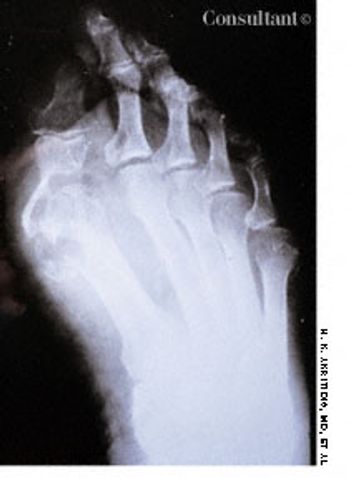

A 72-year-old woman was hospitalized after 8 years of pain and swelling of the right metatarsophalangeal joint. (In this film, the dark area over the distal joint of the large toe is an artifact.) Results of a purified protein derivative tuberculin test were positive, and a chest film revealed apical changes compatible with old tuberculosis (TB).

A 73-year-old man was admitted to the hospital with pain in his hands, feet, and elbows. The patient, an alcoholic, had a 20-year history of hypertension and diabetes. Deformities of the hands and feet had developed during the past 5 years. Tophi were present over both ear lobes. The serum uric acid level was 15 mg/dL.